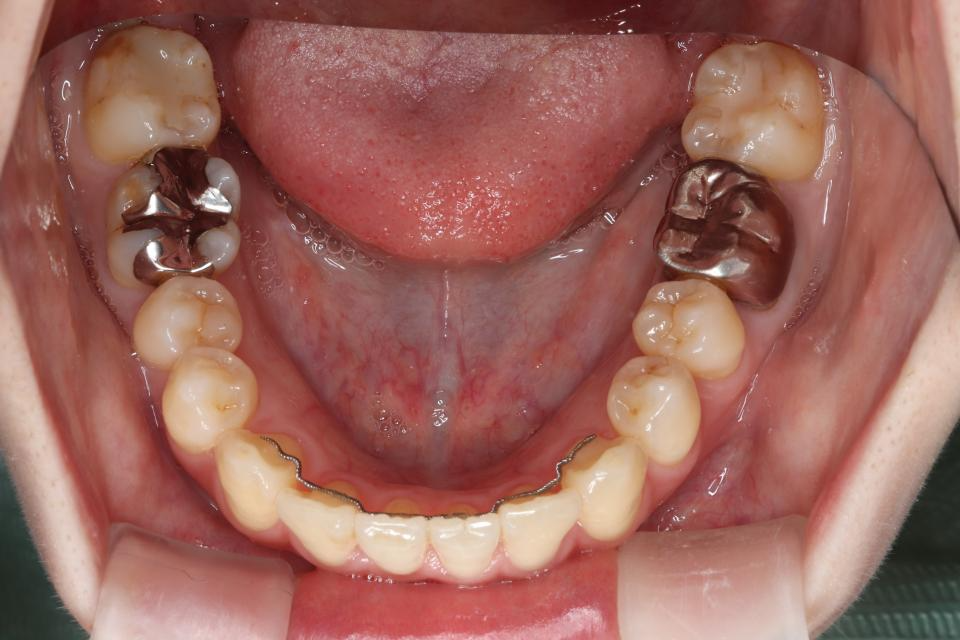

マウスピース型矯正装置による部分矯正治療

矯正治療前

矯正治療後

20代女性です。

上の前歯が2本出ているのが気になると当院に来院されました。

部分的な矯正を希望され、

奥歯の嚙み合わせにも大きな異常はなかったため、

取り外し可能なマウスピース矯正で治療をおこないました。

きれいに並びきるよう歯のやすりがけ(IPR)をしています。

歯を動かす治療は終了し、

現在は上下の前歯の裏側に後戻り防止の針金(FIX)を貼り、

定期的なチェックをしています。